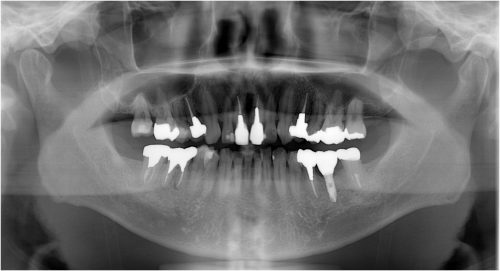

インプラント 右上4567 川口で精密インプラントなら さかえ歯科

川口で精密インプラント治療なら さかえ歯科クリニック